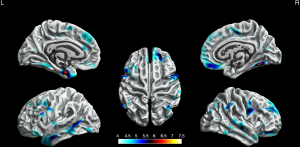

Cortical thickness

Compared with HCs, the BECTS patients showed extensive cortical thinning predominantly in bilateral frontal, temporal regions, and limbic system. These included the superior frontal gyrus, rostral middle frontal gyrus, pars orbitalis gyrus, medial orbitofrontal gyrus, precentral gyrus, fusiform gyrus, middle temporal gyrus in the bilateral hemisphere, parahippocampal gyrus, temporal pole, pars opercularis gyrus, caudal middle frontal gyrus, caudal anterior cingulate gyrus, lateral occipital gyrus and insula in the left hemisphere. Also, it included the superior temporal gyrus, paracentral lobule, inferior parietal gyrus, posterior cingulate gyrus, and inferior temporal gyrus in the right hemisphere (P<0.05, FWE corrected, Figure 1).